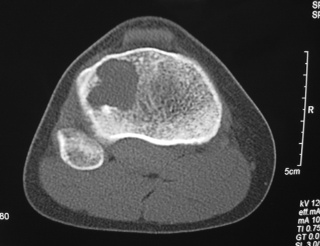

Fig. 4

Fig. 5

Fig. 6

Fig. 7

Fig. 4-7: MR imaging of a benign fibrous histiocytoma of the proximal tibia demonstrates a heterogeneous high signal intensity and low signal intensity with surrounding sclerotic bone on T2-weighted images. T1-weighted images show low signal intensity. No soft tissue mass is visible.